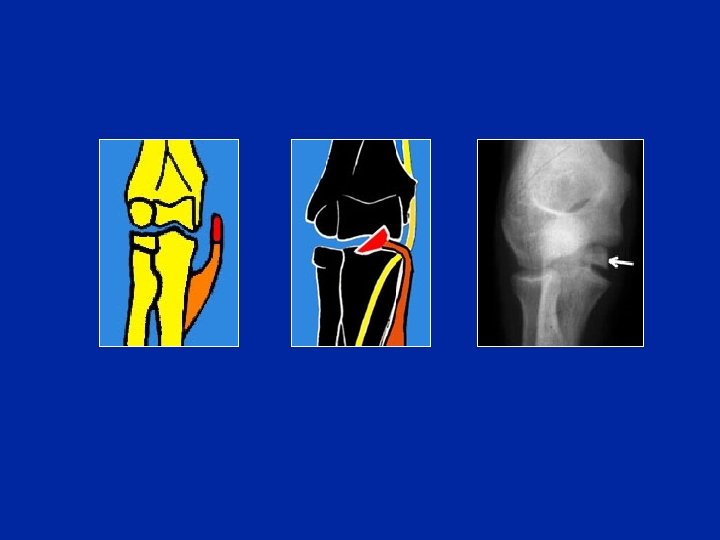

Condilo esterno

Fratture del condilo esterno

(fr di Kocher)